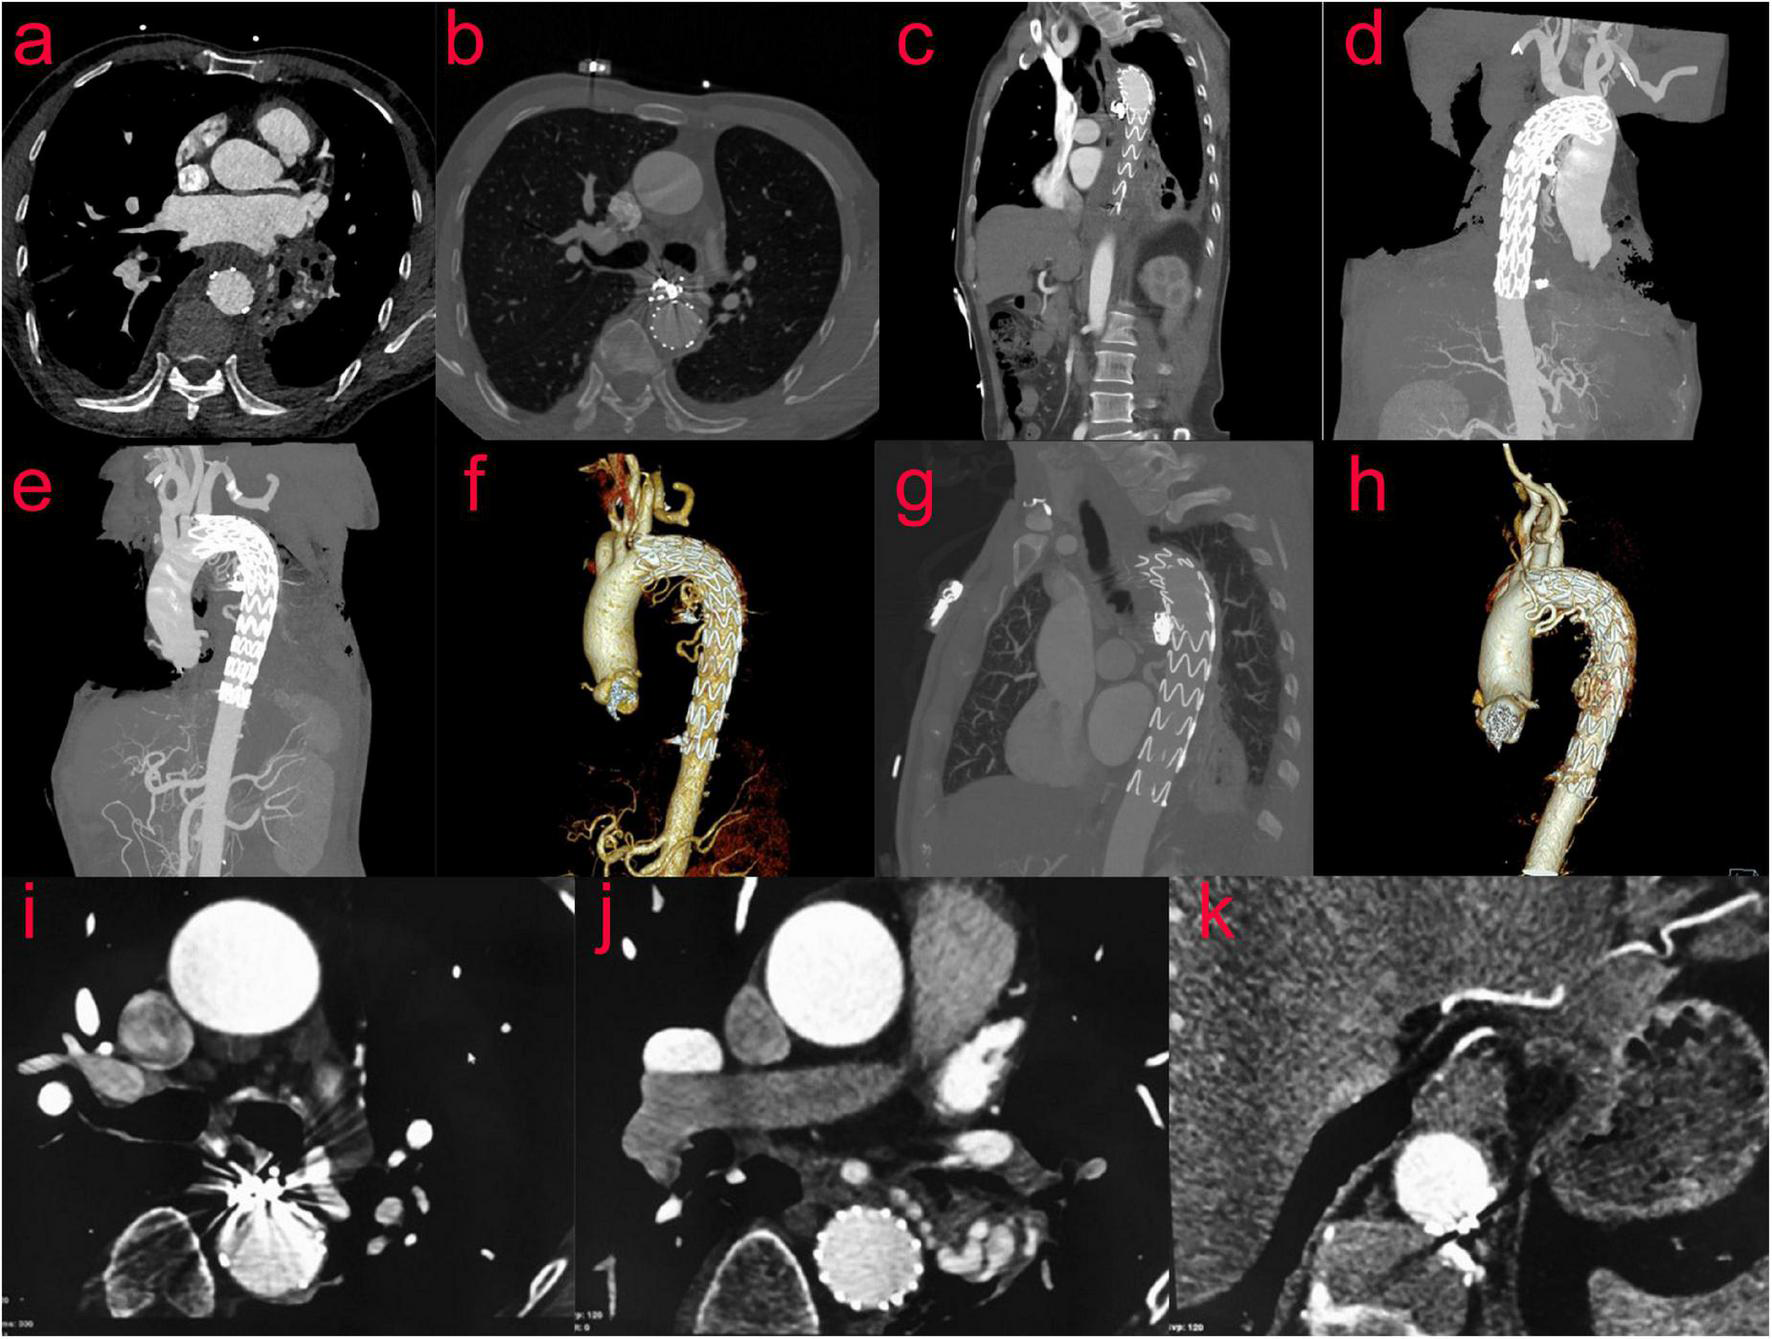

A 65-year-old male patient presented to the emergency department with a 1-day history of retrosternal pain, which was located behind the sternum and was diffuse in scope without fixed location and severe in degree, radiating to the xiphoid process, accompanied by shortness of breath and sweating, occasional cough and sputum. He denied any nausea, hematemesis, or hematochezia. His medical history was retinal detachment. Chest computed tomography angiography(CTA) revealed tortuous and thickened arteries in the posterior mediastinum, hilum of the lung, and left lower lung, which were considered abnormally enlarged and dilated bronchial arteries, accompanied by the formation of proximal aneurysms; therefore posterior mediastinal hematoma was likely (Figures 3a–c,e,f). The laboratory results were as follows: peripheral blood white blood cell (WBC) count was 13.8 × 10^9/L (normal value 4–10 × 10^9/L), C reactive protein (CRP) level was 43.70 mg/L (normal value 0.8–8 mg/L), Hb level was 110 g/L, and erythrocyte sedimentation rate (ESR) level was 85 mm in the 1st h. Troponins and D-dimer were negative. Serum tumor markers were negative. Liver and renal function tests were within normal limits. Coagulation profile was normal.

Thoracic surgery and cardiovascular surgery consultation: patients with bronchial pseudoaneurysm, the neck of the aneurysm is shorter, less than 5 mm, the risk of simple embolization is higher, and the patient is prepared for posterior mediastinal hematoma removal in thoracic surgery in the later stage, and the operation has the risk of rebleeding. Therefore, implantation of covered stent in thoracic aorta was proposed. Bronchial arteriography and coil embolization combined with covered stent graft exclusion of thoracic aorta (Figures 3d,g–l). The results showed that aneurysmal dilatation of the proximal end of the left bronchial artery with a diameter of approximately 2.6 cm; its branches were tortuous and thickened, and the left pulmonary artery branches could be seen; the right bronchial artery thickened and communicating branches were seen between the right and left bronchial arteries. Bronchial arteriography and coil embolization combined with covered stent graft exclusion of the thoracic aorta was performed (Figures 3d,g–l). Microspheres were used for embolization (500–700 um) and coils for embolization were used to occlude the right bronchial artery. After embolizing the left bronchial artery with PVA particles, the left main bronchial trunk and proximal segment aneurysms were embolized with controllable coils. After embolization, the malformed vessels of the left bronchial artery decreased significantly, and the left bronchial artery and aneurysm were almost occluded. A 32/24 × 20 cm covered stent was implanted in the aortic arch and descending aorta. Repeated angiography did not reveal a left BAA. The patient was discharged after 3 days in good general condition.

FIGURE 3

(Case two) A 65-year-old male patient suffered from retrosternal pain for 1 day, the degree was severe, and the scope was diffused. Bronchial arteriography (d,g,h) was performed after examination of the chest CTA (a–c,e,f). The aneurysmal dilatation of the proximal end of the left bronchial artery with a diameter of approximately 2.6 cm. Its branches were tortuous and thickened. The left pulmonary artery branches were seen. The right bronchial artery thickened, and the communicating branches were seen between the right bronchial artery and the left bronchial artery. The embolization operation and the thoracic aorta-covered stent implantation were performed. Percutaneous catheterization of left and right femoral artery under general anesthesia and local anesthesia, left and right bronchial artery, and thoracic aorta were performed. Digital subtraction angiography showed that the right bronchial artery was embolized by embolized microspheres (500–700 um) and coils, and the left bronchial artery was embolized by two branches of PVA particles (700 um) (i,j). The left bronchial trunk and proximal segment aneurysms (k) were embolized with controllable coils, and a 32/24 × 20 cm covered stent (l) was implanted into the aortic arch and descending aorta through the left femoral artery.